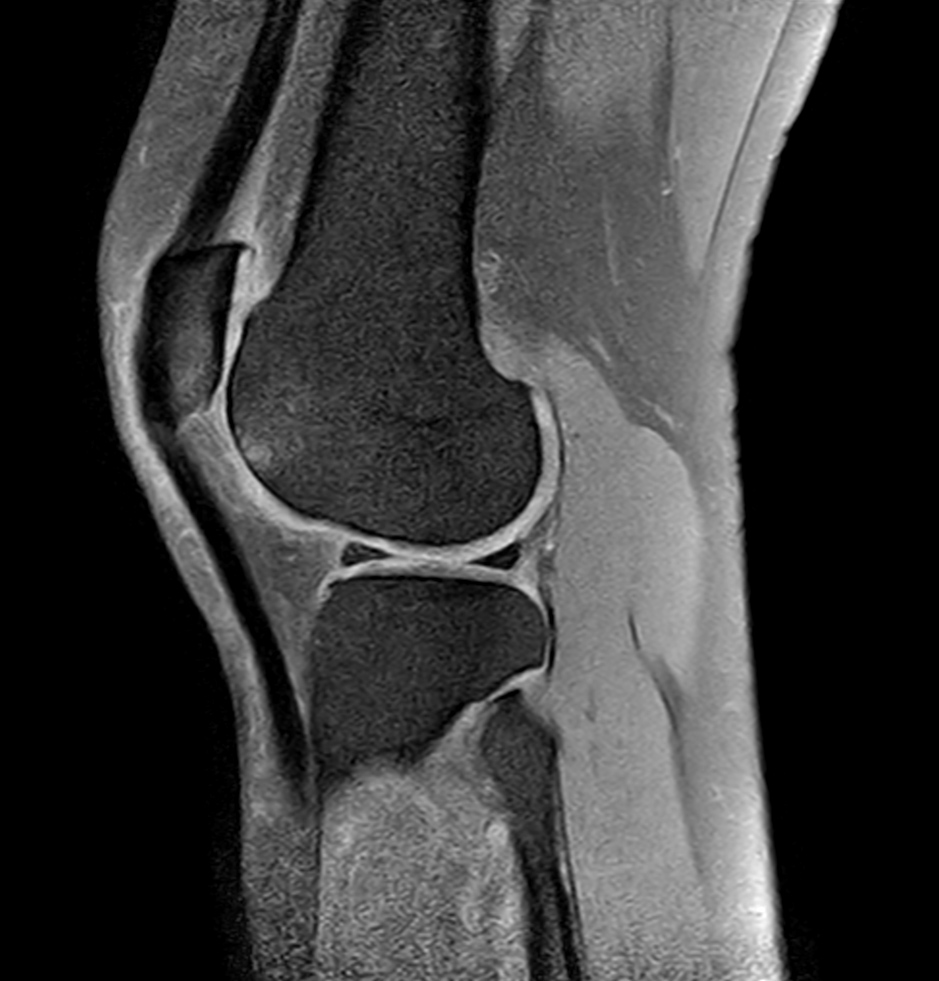

Coronal T1w TSE